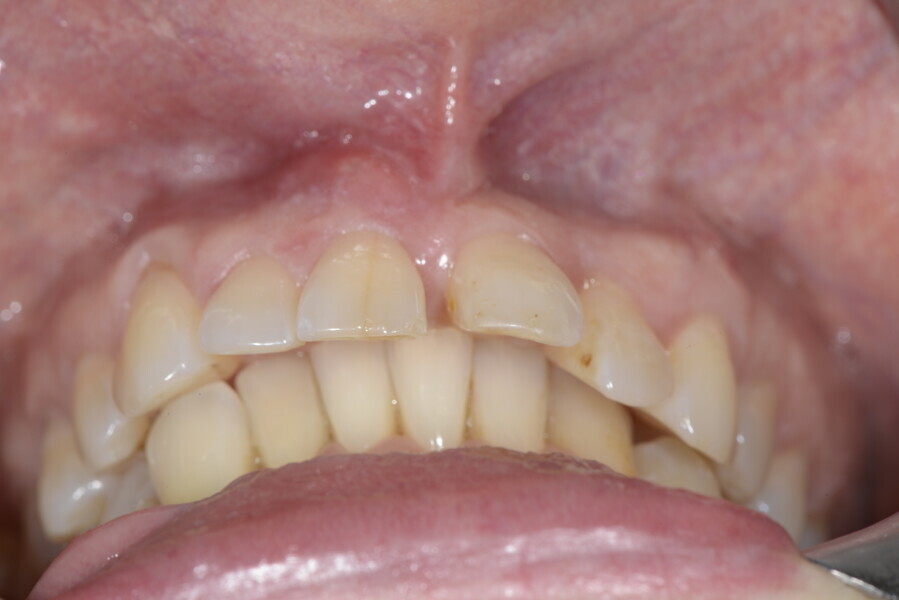

The 58-year-old patient wished to improve his oral aesthetics and function, complaining of mobility of the posterior teeth and wear of the anterior teeth. After data collection, a very complex situation was identified (Figs. 11–13):

1. severe periodontitis with poor prognosis of some teeth;

2. anterior crossbite;

3. severe wear mainly of the anterior teeth and compensatory eruption;38

4. atypical swallowing and lower posture of the tongue at rest;

5. masticatory dysfunction during the mastication test; and

6. no significant signs of temporomandibular disorder.